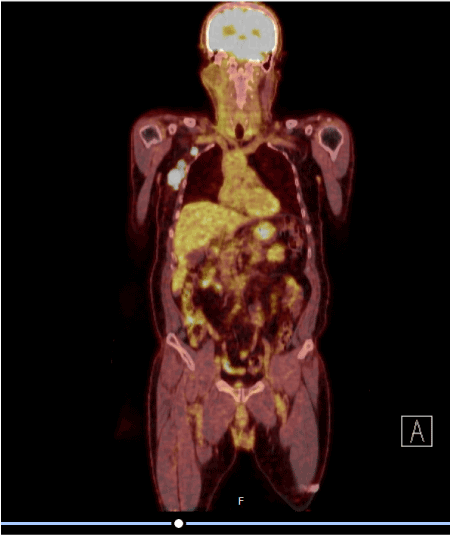

The patient's Positron emission tomography (PET/CT) showed multiple lymphadenopathies with a diameter of 3.6 cm with pathological glucose metabolism increases in the right axillary region Standardized Uptake Value (SUVmax: 42.6). Pathologic glucose metabolism increases were observed in 2 adjacent lymph nodes (SUVmax: 31.9) in the right infraclavicular region (Figures 1 and 2).

Figure 1. Image of first relapse after curative treatment

Figure 2. Image of first relapse after curative treatment